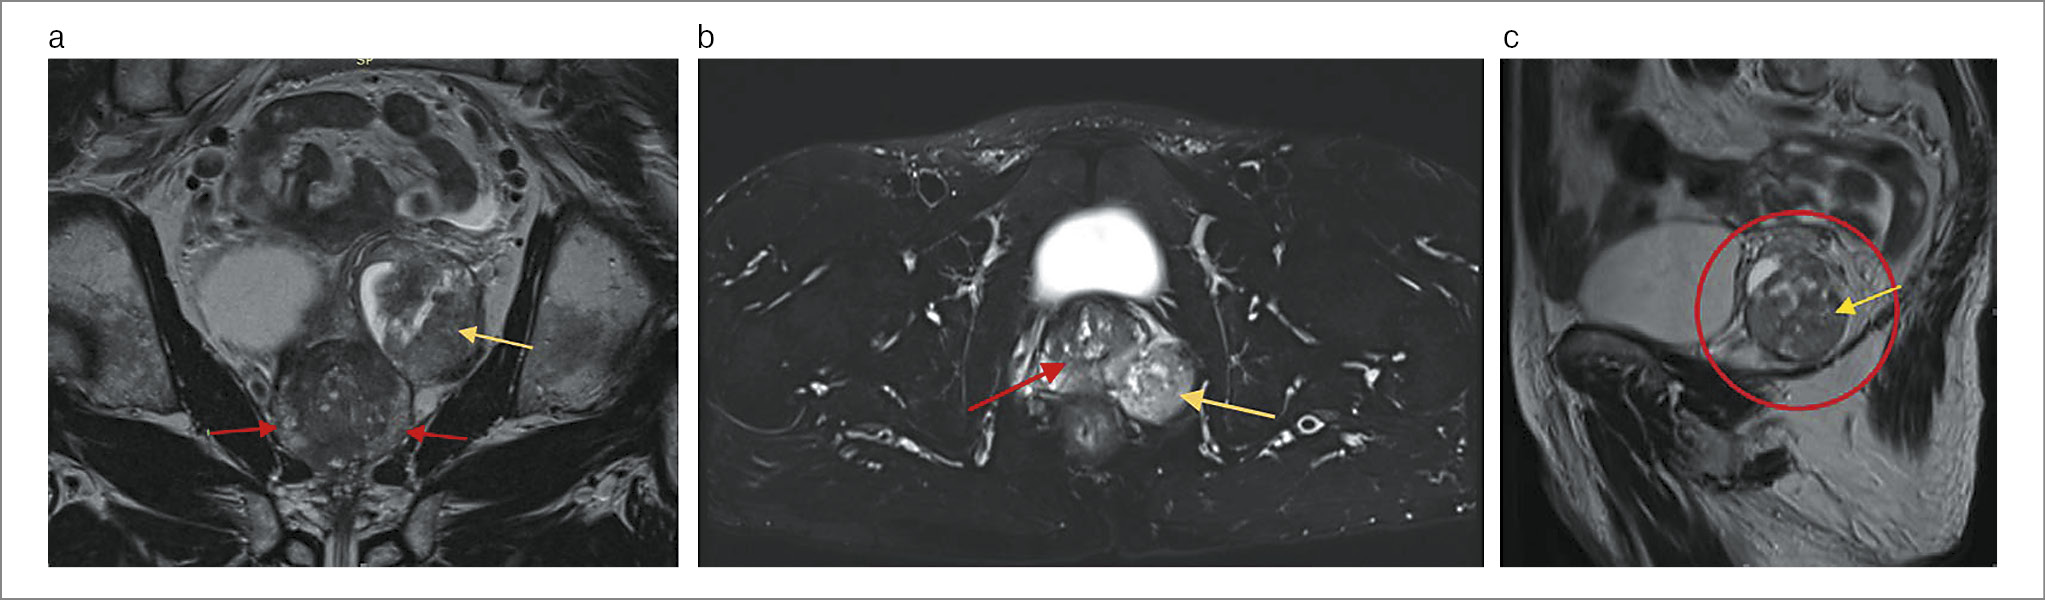

В проекции левого семенного пузырька определяется кистозно-солидное узловое образование размерами 40×42×51 мм, достигающее стенки таза и брюшины. Правый семенной пузырек не изменен. Лимфоузлы таза и паховые лимфоузлы не увеличены (рис. 1). Заключение: магнитно-резонансные признаки мультифокального инвазивного опухолевого поражения ПЖ, крупное образование левого семенного пузырька специфического характера.

Рис. 1. Пациент М. На коронарной (a), аксиальной (b), сагиттальной (c) МРТ-проекциях малого таза с контрастированием в проекции семенного пузырька слева – кистозно-солидное образование размером 40×42×51 мм (желтая стрелка), в обеих долях ПЖ – множественные очаговые образования до 20 мм (красная стрелка).